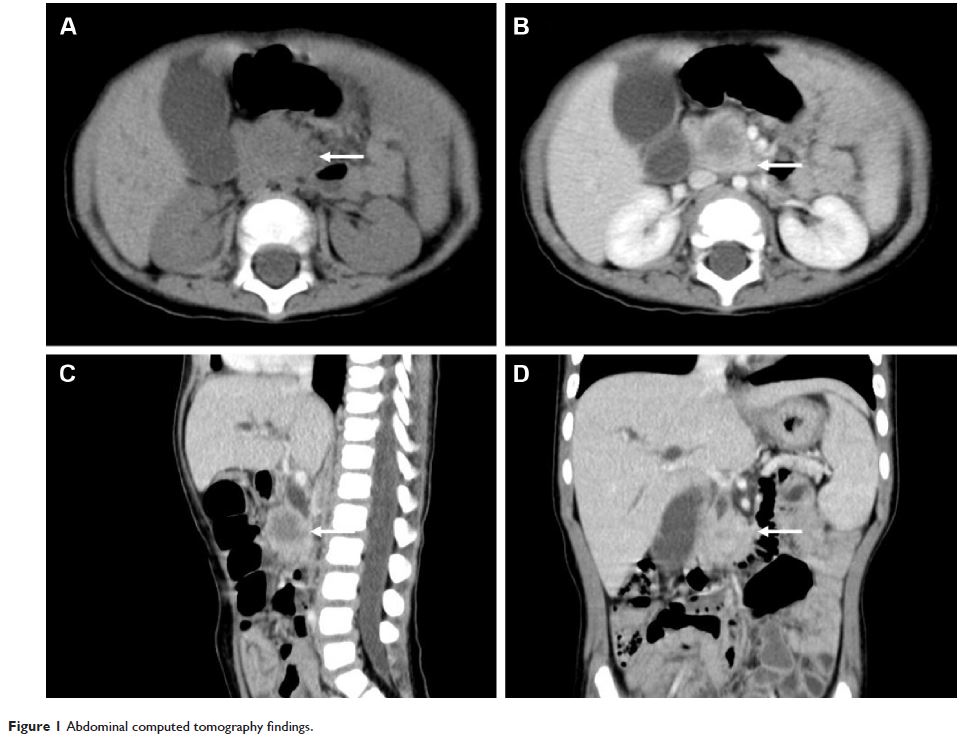

Case Report

- 作者:Qingfeng Sheng, Weijue Xu, Jiangbin Liu, Baiyong Shen, Xiaxing Deng, Yibo Wu, Wei Wu, Shenghua Yu, Xueli Wang, Zhibao Lv

- 期刊:OncoTargets and Therapy